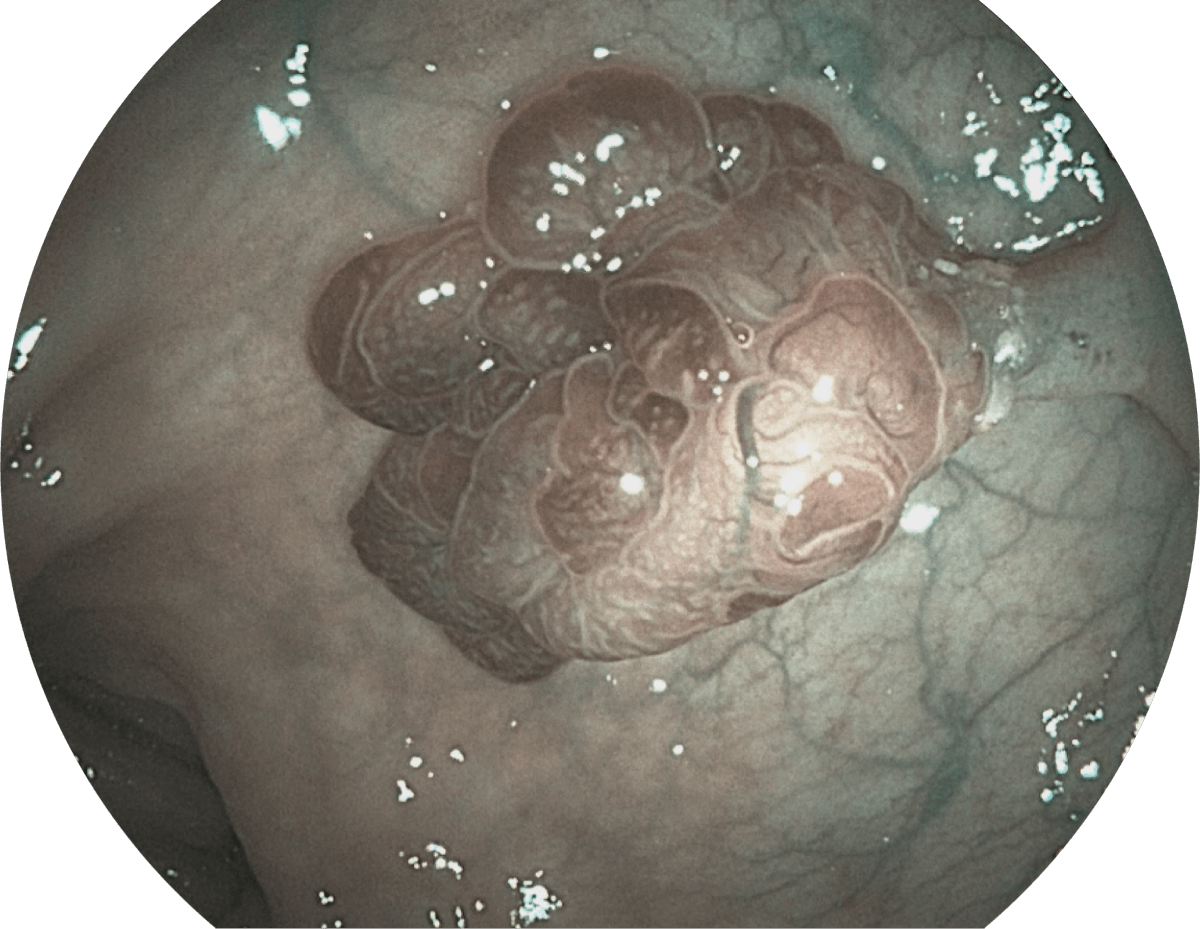

• 光电复合染色成像技术

( Versatile Intelligent Staining Technology, VIST )

强调浅层黏膜结构的同时,保证照明亮度和提升浅层微血管与中层血管颜色对比度,病变边界更清晰。

• WL

• SFI

• VIST